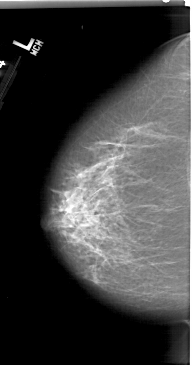

A_1411_1.LEFT_CC

LEFT_CC LINES 6571 PIXELS_PER_LINE 3451 BITS_PER_PIXEL 12 RESOLUTION 43.5 NON_OVERLAY